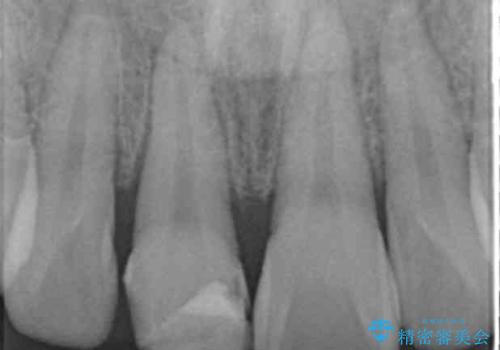

歯の神経の状態を見たところ、前歯3本とも神経が死んでしまっていました。

根の治療を行い、ぐらつきに関しては様子を見て連結をするとのお話をさせていただきました。

今後事故の影響でほかの歯の神経が死んでしまったり、状態が変化する可能性があるため経過観察が大事になってきます。